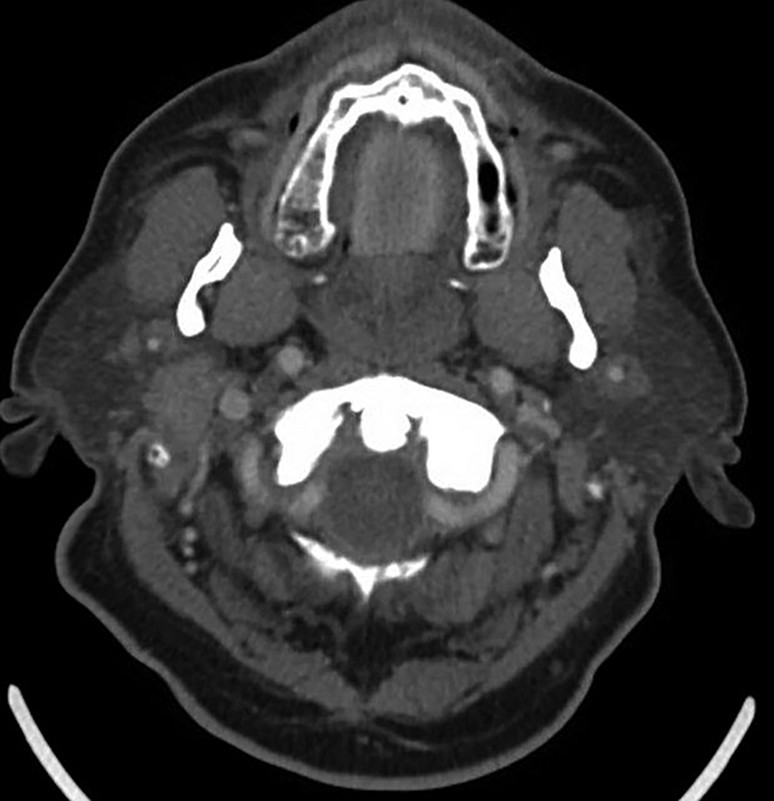

Presented live on Sunday, April 16 during the 2023 ARRS Annual Meeting in Honolulu, HI, our “The Suprahyoid Neck—Pathology Through Anatomy” Featured Session will focus on reviewing important anatomical subunits and common pathologies of the suprahyoid neck: the parapharyngeal, pharyngeal mucosal, masticator, parotid, carotid, retropharyngeal, danger, and perivertebral spaces (Fig. 1).

Examining imaging findings crucial for diagnostic radiologists and neuroradiologists alike to identify, attendees will enhance their clinical performance through a greater, more holistic understanding of cross-sectional anatomy and common pathologies that lead to various lesions in these regions—each a critical check point for accurate interpretation of radiological studies of the suprahyoid neck.